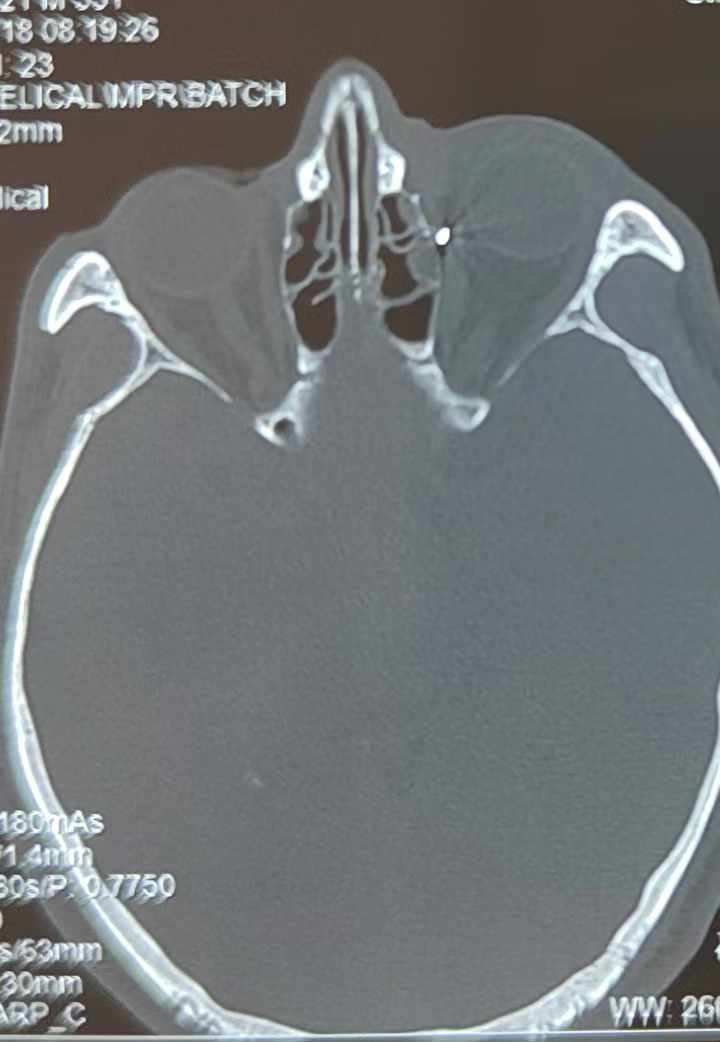

裝修工人高先生在作業(yè)過程中不慎被砸傷左眼,送至廈門眼科中心救治時,眼外傷及眼底病2科副主任醫(yī)師李海波博士在CT檢查報告中發(fā)現,進入眼內的異物在眶尖極為隱匿的位置,想要“不動聲色”地取出來,有些難度。

從CT報告中可以看出,高先生眼內的異物不是很大,但位于眼窩深處,緊鄰鼻骨,從CT影像判斷應該是金屬或合金異物。一般臨床上遇到這樣的情況,醫(yī)生會建議“保守觀察”,若異物傷及神經、發(fā)生炎癥感染等,則需到條件較好、有眼眶病和眼外傷專業(yè)醫(yī)師的醫(yī)院進行二期眶內異物取出術(2021年《中國眼眶異物診斷和治療專家共識》)。

李海波博士介紹,眶內異物想要通過手術取出,難度很大,一是因為位置隱匿,無法實現可視化操作;二是如果是磁性異物,現有手術工具磁性強度有限,很難吸出這么深的異物;三是可操作空間極為狹小,眶周軟組織多,異物周邊包裹緊密,像高先生這種情況,異物周邊還有很多神經、血管,手術難度更高。

手術十分順利,李海波博士設計好了取出路徑,用這根細磁棒取出了一個米粒大小的鐵屑,過程中未造成二次傷害和大創(chuàng)面?zhèn)?。術后CT檢查顯示,高先生眼內再無異物,他此時才松了一口氣。